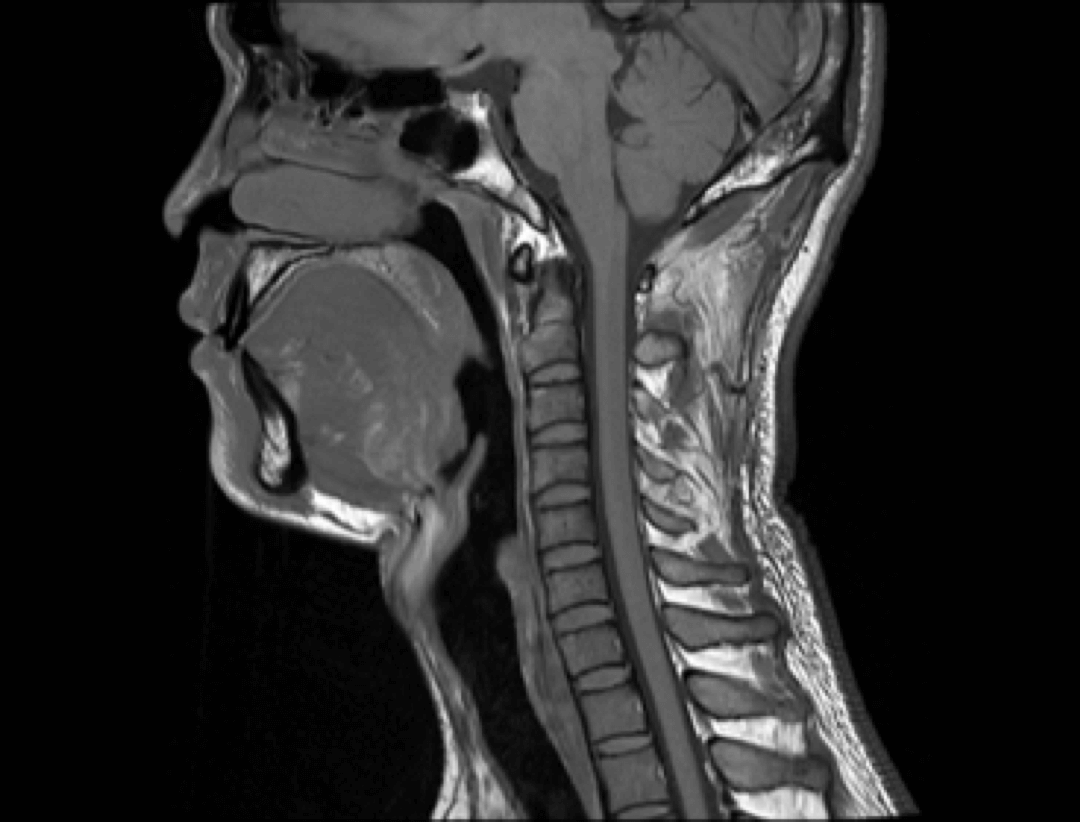

Spine